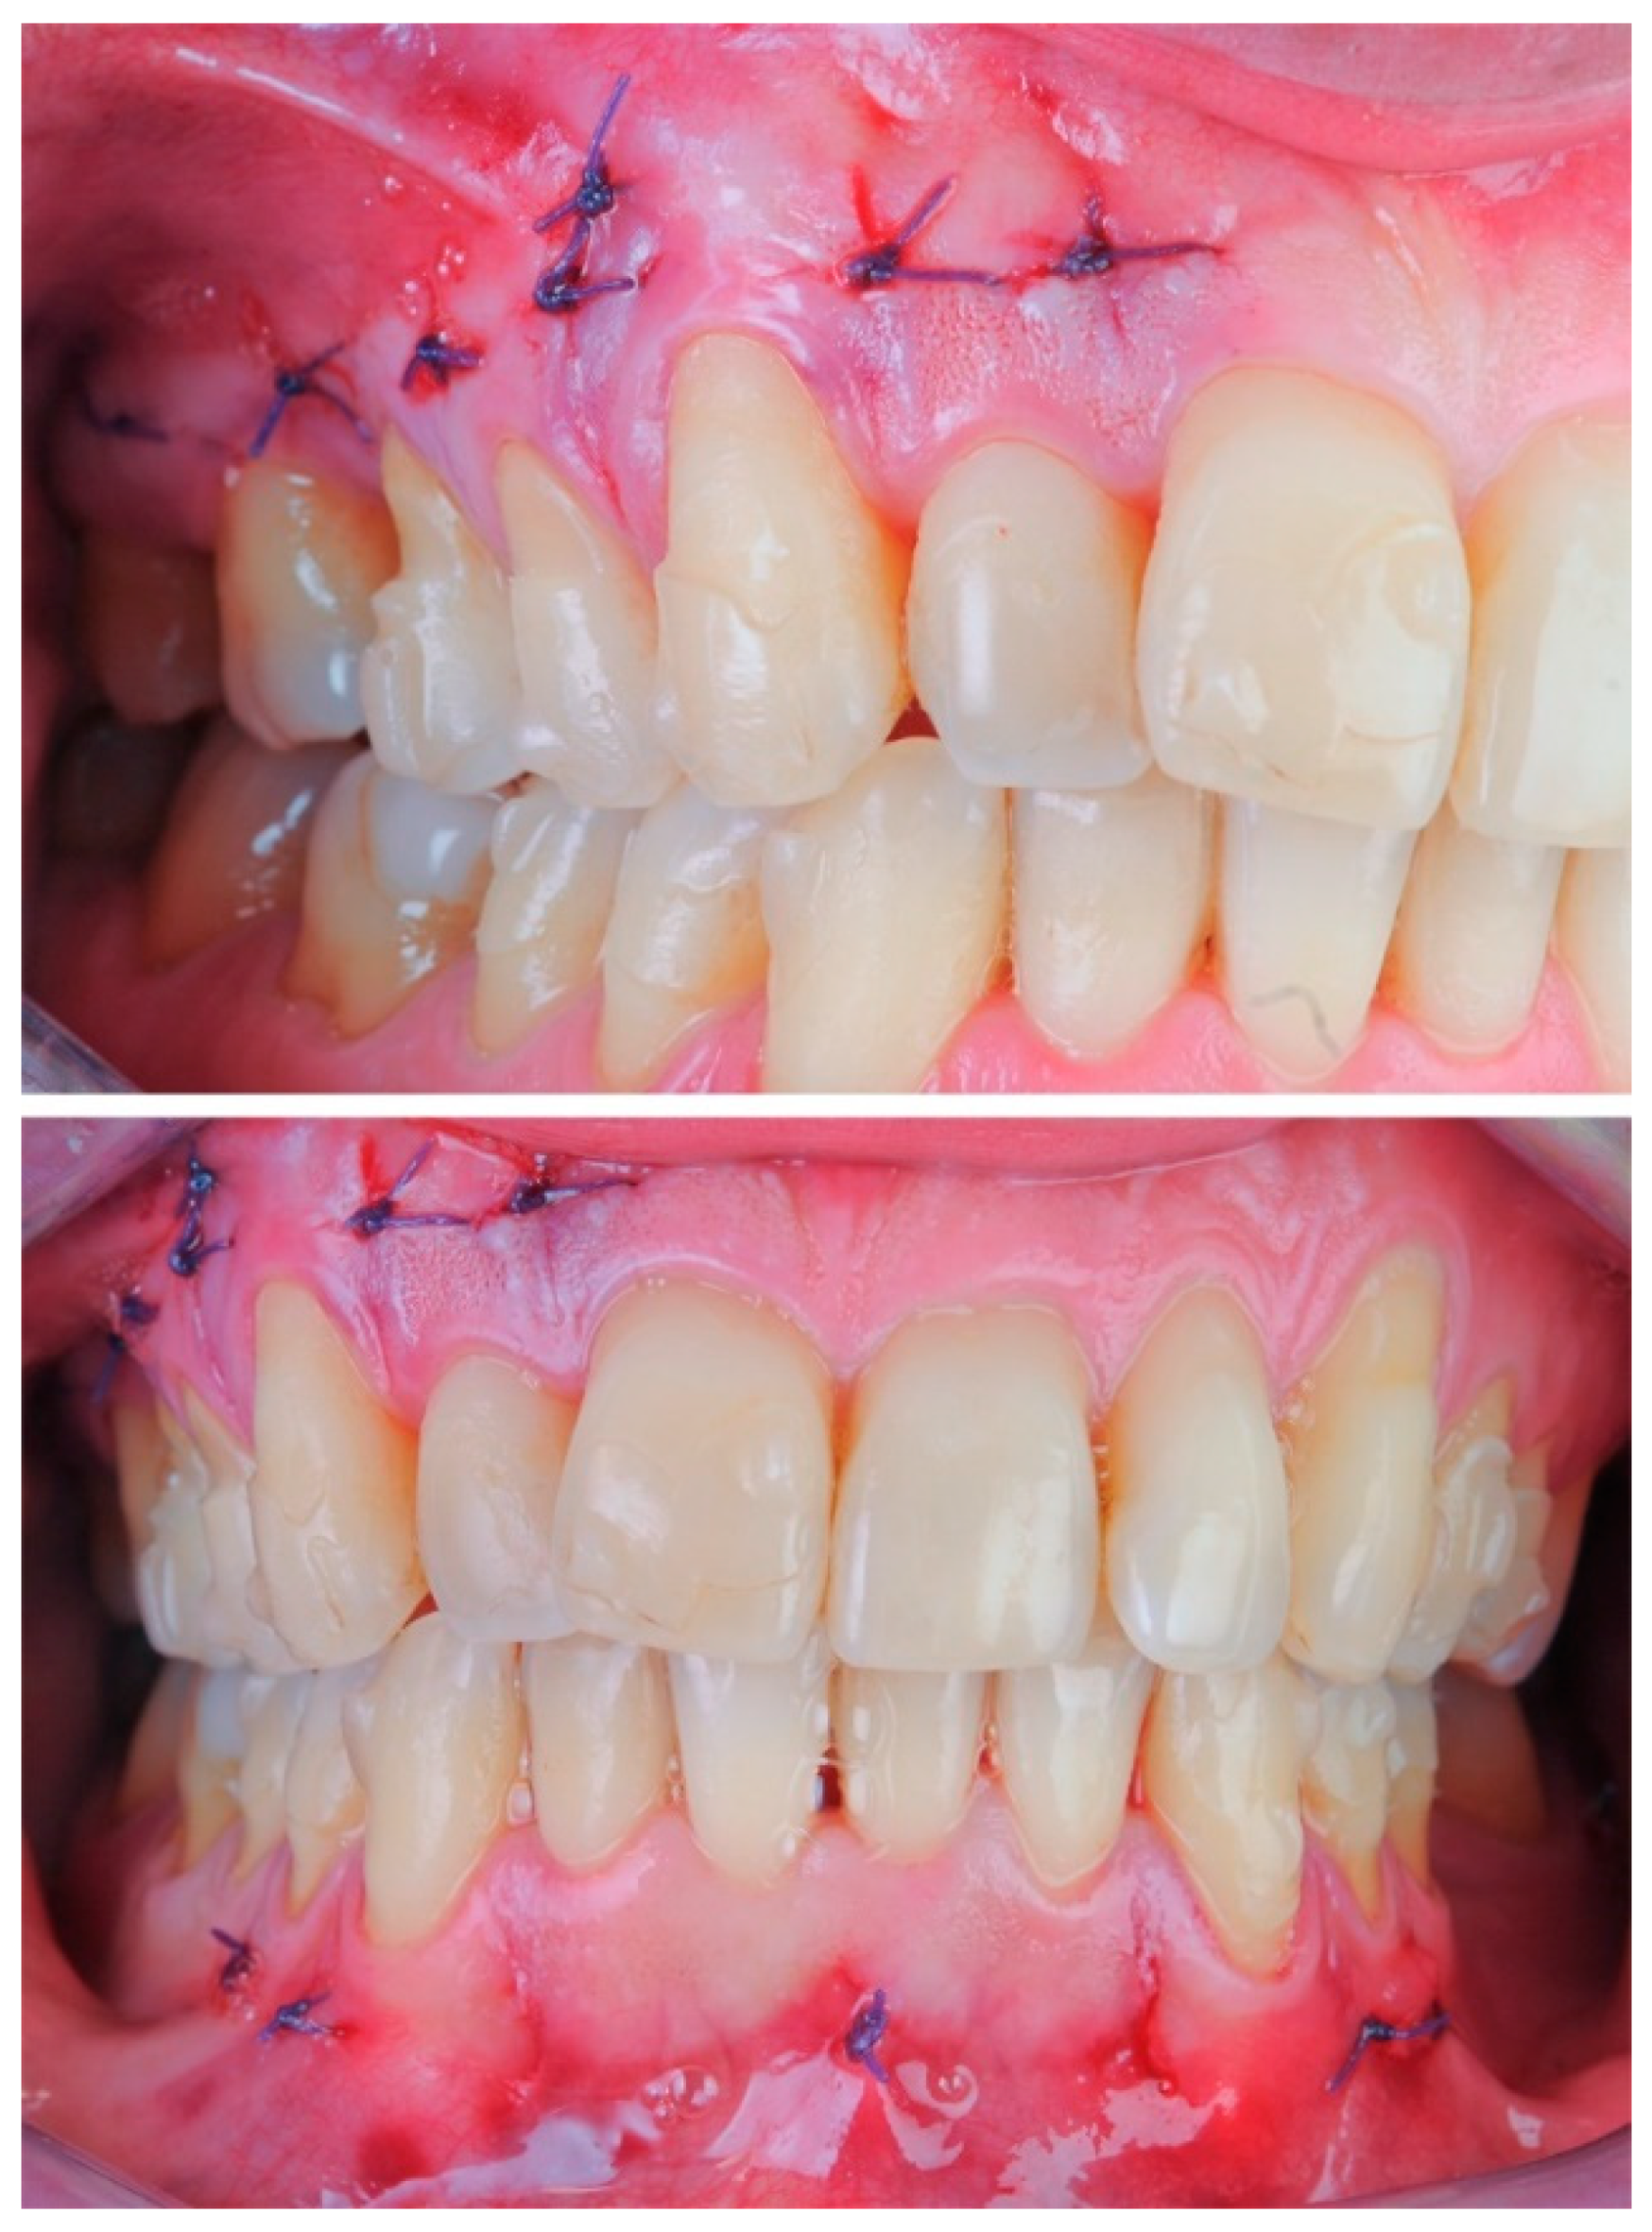

2.3. Surgical Procedure

2.3.1. Example—Anterior Open-bite

2.3.2. Example 2—Extraction Space Closure